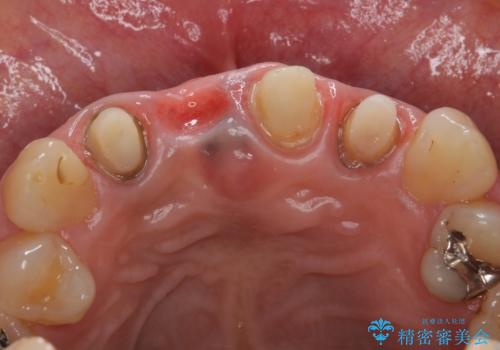

- 右上の前歯が折れてしまったので診て欲しいといらっしゃった方の症例です。

右上1番目の歯は保存不可能だったため抜歯し、ブリッジによる補綴を行いました。

- オールセラミッククラウン(スペシャル)…¥130,000×4、仮歯…¥10,000×4、ファイバーコア…¥20,000×3、精密根管治療費別途費用は治療当時の料金となります